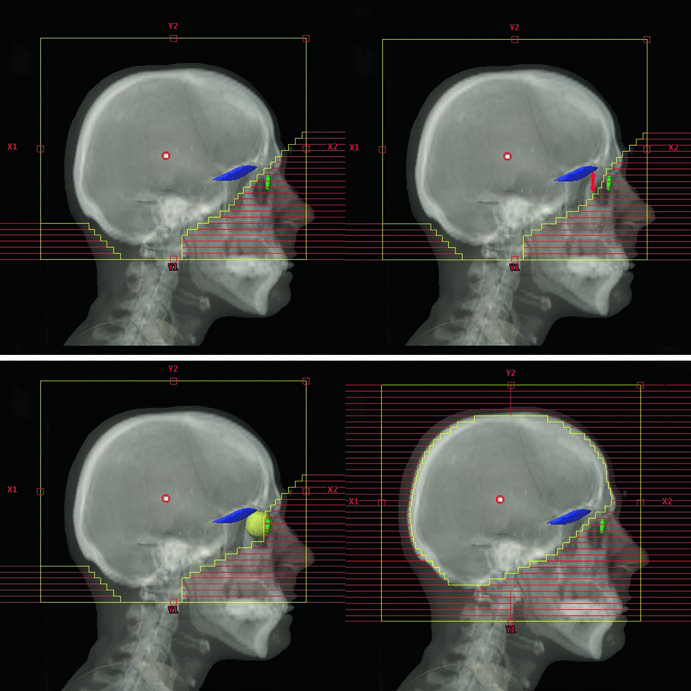

Cenários Clínicos e Campos Sugeridos para WBRT

O planejamento muda conforme o cenário clínico. Metástases difusas (numerosas ou “incontáveis”) e PCI para SCLC recebem campos convencionais. Doença leptomeníngea exige cobertura adicional dos nervos ópticos, região retroorbital e lâmina cribosa, com margens expandidas de 8–10 mm para penumbra e setup diário nos lobos temporais e placa cribiforme. A leucemia e o linfoma de SNC demandam inclusão da retina e, se houver envolvimento ocular confirmado por exame de lâmpada de fenda, cobertura dos globos oculares inteiros.

| Doença Leptomeníngea | 3D-CRT lateral oposta | Conteúdo craniano + nervos ópticos + região retroorbital + lâmina cribosa | Lobos temporais e placa cribiforme com margem adicional de 8–10 mm para penumbra e setup |

| Linfoma/Leucemia de SNC | 3D-CRT lateral oposta | Conteúdo craniano + nervos ópticos + região retroorbital + retina ± globos inteiros | Posterior 1/3 dos globos se sem envolvimento ocular; globos inteiros se envolvimento confirmado |

| Scalp-Sparing | 3D-CRT lateral oposta | Conteúdo craniano inteiro | Borda do MLC posicionada na tábua externa da calvária |